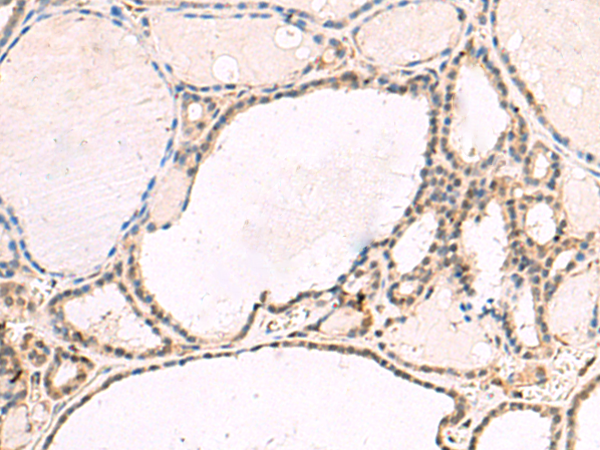

分类: 科研抗体货号: P10117别名: RTA; fxh; FOX2; RBM9; Fox-2; HNRBP2; HRNBP2; dJ106I20.3应用: IHC反应种属: Human, Mouse, Rat